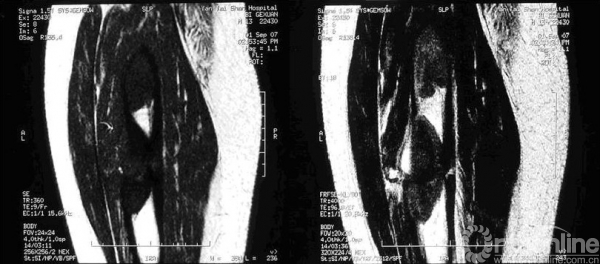

MRI表现比较复杂,根据病灶内所含组织的比例不同,表现也不同,多数表现为T1WI和T2WI呈不均匀的低信号,T2WI压脂像上呈中等信号(图8),病灶内有出血或积液时信号明显增高,MRI非常敏感,可早期诊断,并能清楚的确定肿瘤的范围,但对骨皮质的显示不清楚(图9)。

图8 MRI示T1和T2主要为低信号

图9 X线片显示不明显,而MRI可清楚显示